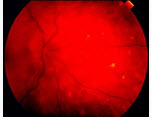

后葡萄膜炎(如图)常见的临床表现()

A:眼前星影、闪光、视物模糊

B:房水闪辉、角膜后KP、虹膜纹理不清、有渗出

C:玻璃体混浊

D:局灶性脉络膜视网膜浸润病灶

E:视网膜血管炎、黄斑水肿